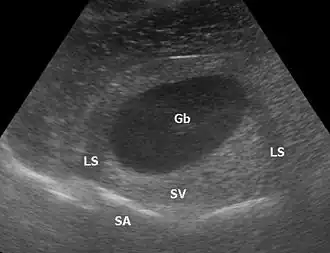

Eine distale Schallverstärkung ist ein übermäßig hell dargestelltes Gewebe hinter (distal) einer Struktur, die wenig dämpft. Allgemein wird, um die Dämpfung des Gewebes auszugleichen und zum Beispiel Lebergewebe über die gesamte Tiefe homogen darzustellen, mit Hilfe der time gain compensation oder auch depth gain compensation, tiefer liegende Signale zunehmend verstärkt. Zum Beispiel bei einer Gallenblase in der Leber ist das Lebergewebe deutlich heller als das restliche Lebergewebe, weil Galle weniger dämpft als Lebergewebe, aber das Gewebe hinter der Gallenblase mit dem gleichen Verstärkungsfaktor aufgehellt wird wie das umliegende Gewebe.

Bei kreisförmig geschnittenen Objekten können die Randstrahlen weggespiegelt werden; dem Bild fehlen dann die Randstrukturen und es kommt zu Abschattungen (engl.: lateral shadowing).